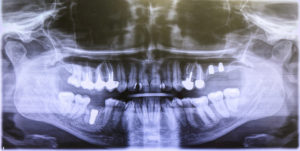

Our oral surgeon, Dr. Donnie Quick, at Arkansas Oral Surgery in Fort Smith, Arkansas is extensively trained in managing a wide range of facial trauma cases, from fractured jaws and cheekbones to soft tissue injuries and displaced teeth. We begin with a thorough assessment, utilizing the latest diagnostic tools to evaluate the extent of the damage with precision. This allows us to develop a tailored treatment plan, whether it involves realigning broken bones, repairing lacerations, or addressing dental injuries. Our expertise ensures that both structural integrity and facial symmetry are restored effectively.

Precision is critical in facial trauma treatment, and we employ state-of-the-art techniques to achieve the best outcomes. For fractures, we use biocompatible plates and screws to stabilize bones, promoting proper healing with minimal scarring. Soft tissue repairs are performed with microsurgical methods to preserve appearance and function. We also address dental trauma, such as avulsed (knocked-out) teeth, with immediate care to maximize the chance of successful reimplantation. Sedation or general anesthesia is expertly administered to ensure patient comfort during these complex procedures.